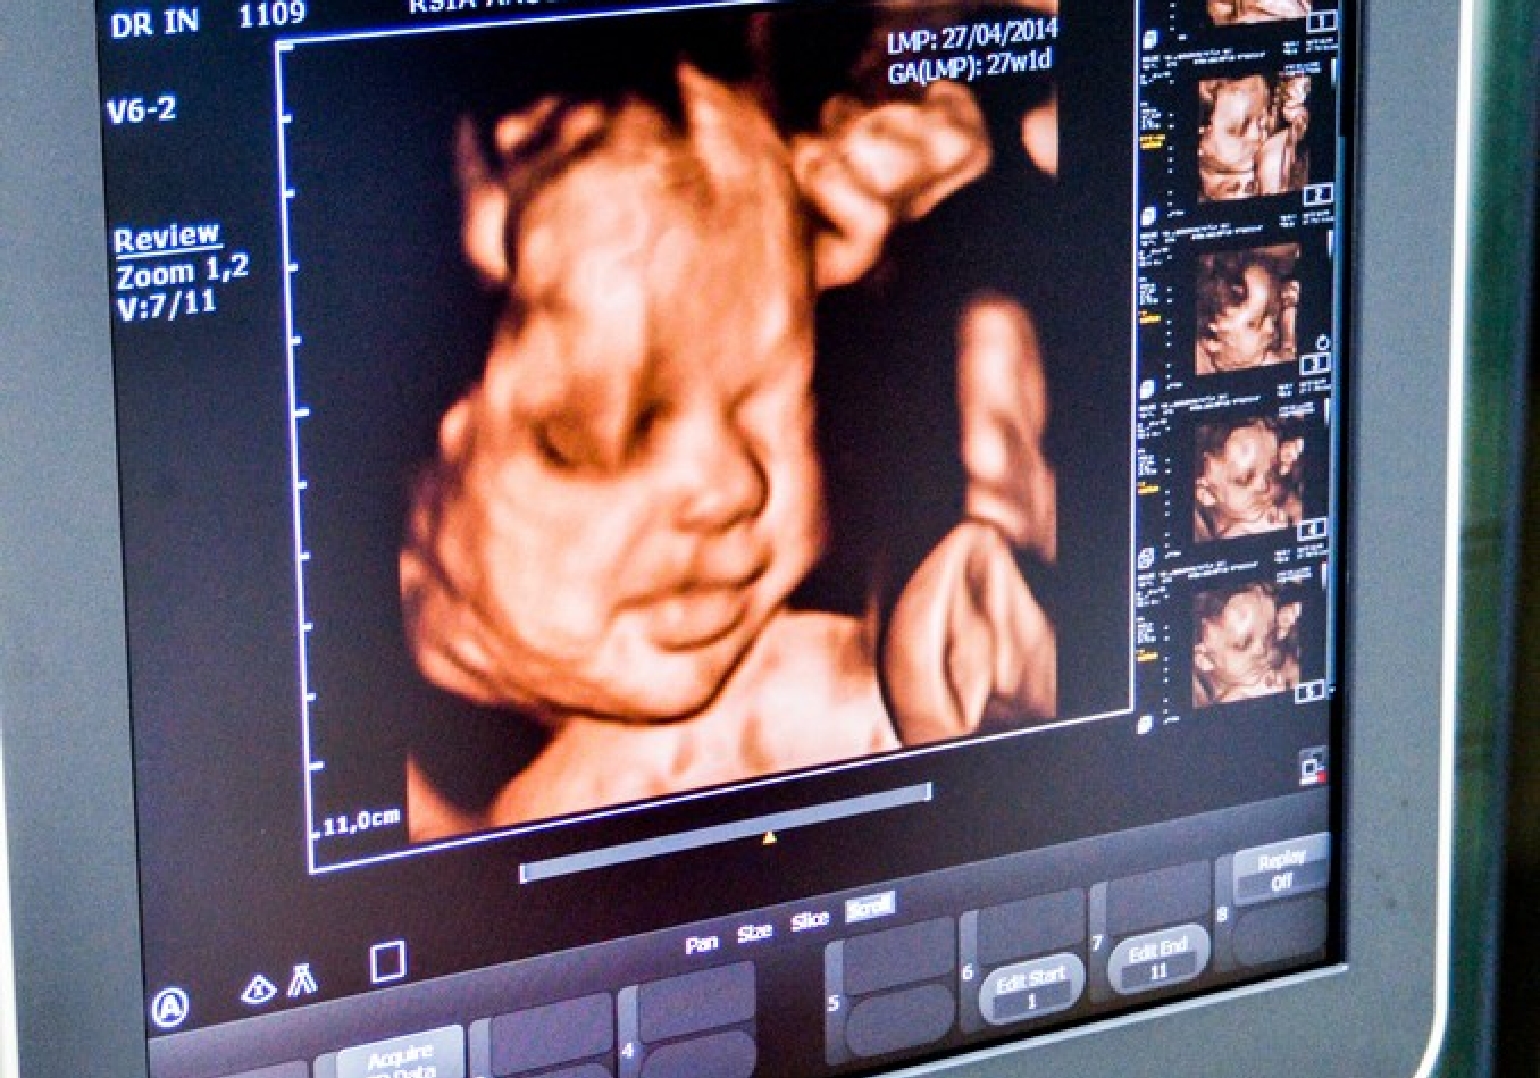

USG 3D/4D dan Pemeriksaan Kelainan Bawaan

Kami dapat menampilkan citraan terbaik dari janin dalam kandungan Anda menggunakan USG 3D / 4D. Kami percaya bahwa sangatlah penting untuk memberikan pemeriksaan yang komprehensif pada kesehatan dan pertumbuhan janin. Berikut adalah beberapa foto dari peralatan dan fasilitas yang kami miliki